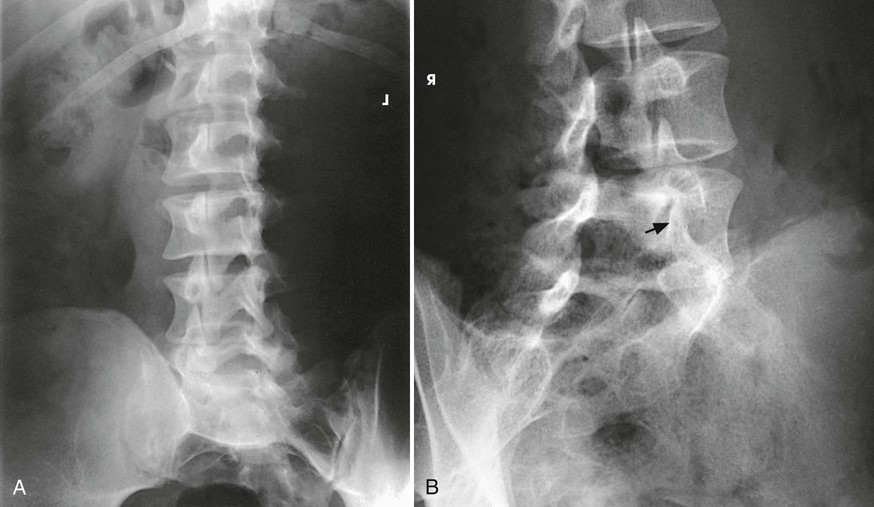

Structures shown

The image shows the lumbar bodies and their intervertebral disk spaces, the spinous processes, and the lumbosacral junction (Fig. 8-92). This projection gives a profile image of the intervertebral foramina of L1-4. The L5 intervertebral foramina (right and left) are not usually well seen in this projection because of their oblique direction. Consequently, oblique projections are used for these foramina.

The resulting image shows a lateral projection of the lumbosacral junction, the lower one or two lumbar vertebrae, and the upper sacrum (Fig. 8-94).